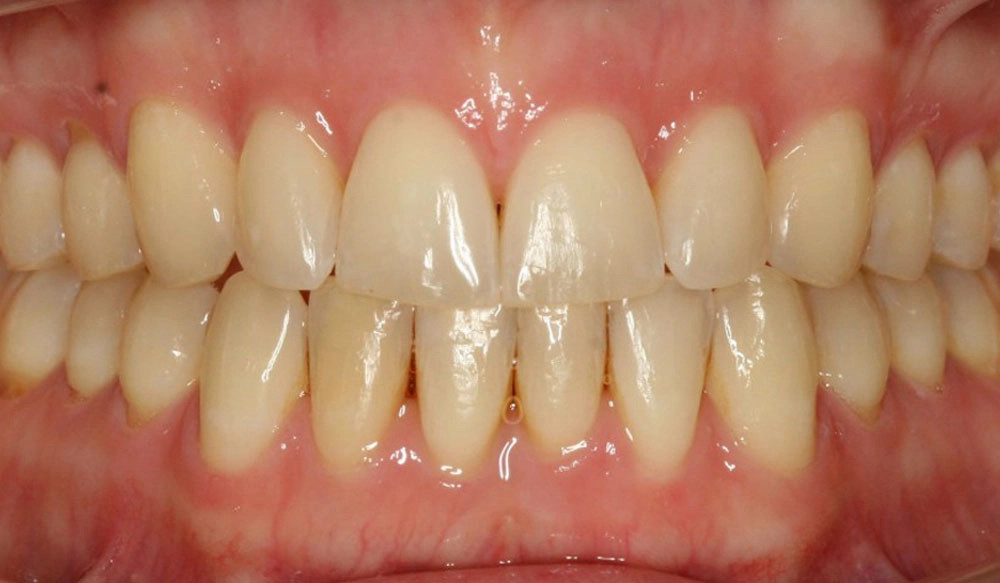

Crowding

Crowding is the condition in which there is a discrepancy between tooth size and space available for the teeth to be aligned in the dental arch

Patient Information:

Age: 17

Gender: female

Invisalign Treatment Option: Invisalign Comprehensive

Total Treatment Time:

29 months